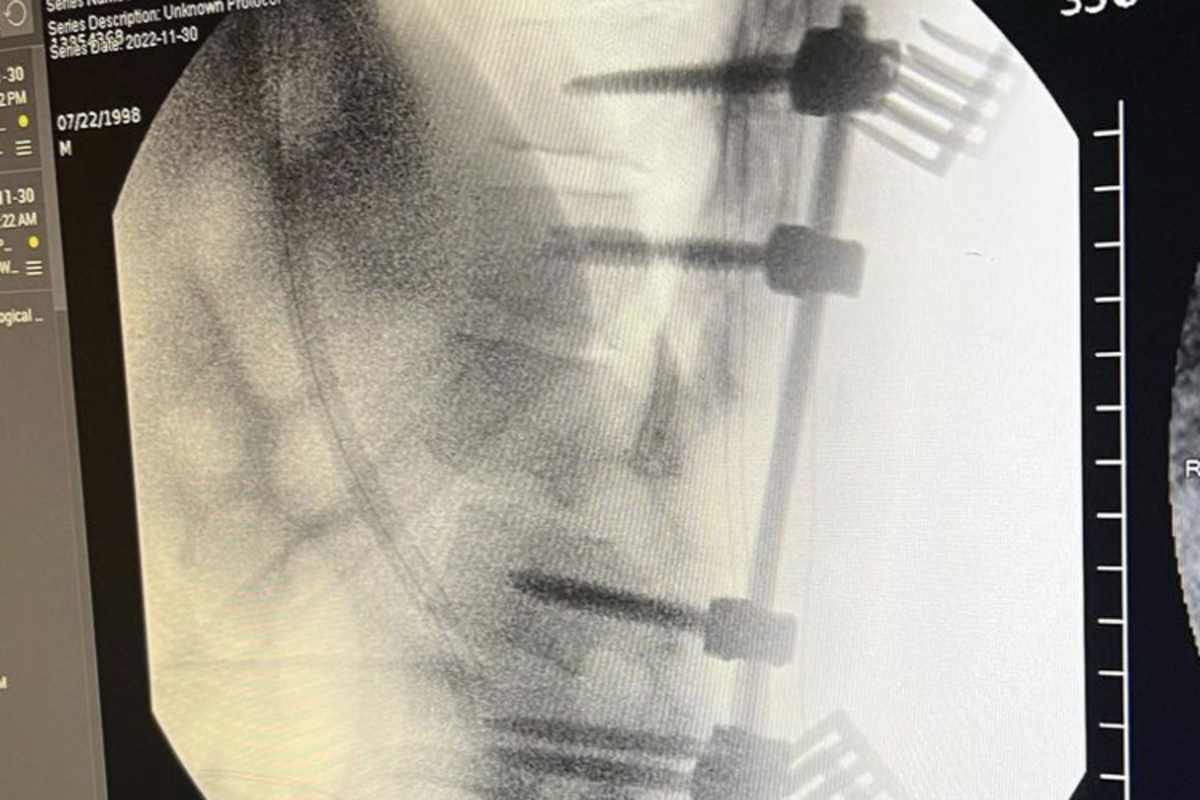

"Es geschah in einer Rhythmussektion von 3 Dreifachsprüngen", erklärte Hartranft. "Ich bin am zweiten Sprung mit dem Kopf voran eingeschlagen." Er zog sich mehrere Wirbelbrüche zu: Die Lendenwirbel L1 und L2 sind gebrochen. Die Querfortsätze der Lendenwirbel L3 und L4 sowie die Dornfortsätze der Lendenwirbel L1, L2 und L3 sind gebrochen. Das linke Hüftgelenk ist ausgekugelt. Außerdem sind mehrere Rippen und das rechte Schulterblatt gebrochen. Zudem hat er einen Hämatothorax erlitten.

Hartranft wurde am Donnerstag operiert, um die Wirbelsäulenverletzungen zu stabilisieren. Sein Zustand ist stabil und hat Gefühl in den Beinen.